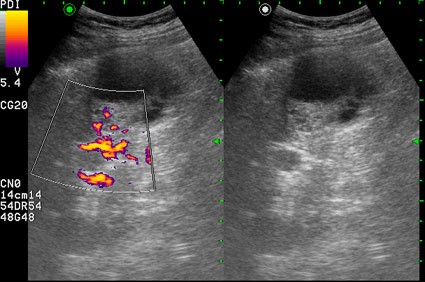

Сонограмма правой почки у женщины 42 лет. Женщина болеет сахарным диабетом, профилактический осмотр.

Как трактовать выявленные изменения? Какова тактика врача УЗД в данной ситуации?

по Bosniak-type3-indetrminate lezion- показана биопсия

Почечно-клеточный рак, тип "опухоль в кисте" ?

RCC. Тип "опухоль в кисте".